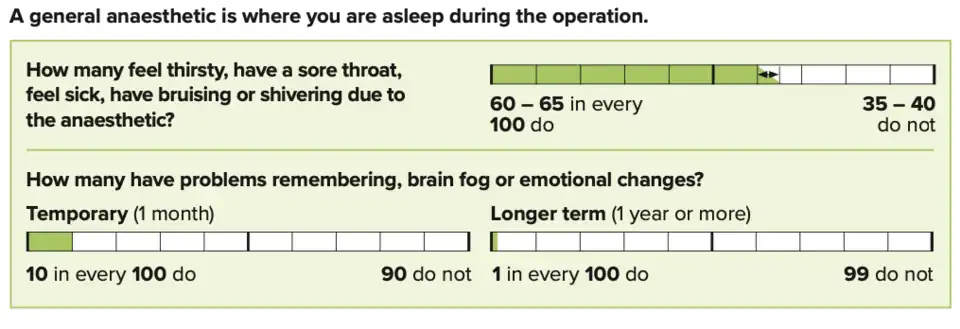

Additionally, certain medical conditions can prevent people from being candidates for laparoscopic approaches to repair. Examples of such include:[19][10][12]

- People who are unable to undergo general anesthesia

- risks of general anaesthetic (used for laparoscopic hernia repair and most open hernia repairs)